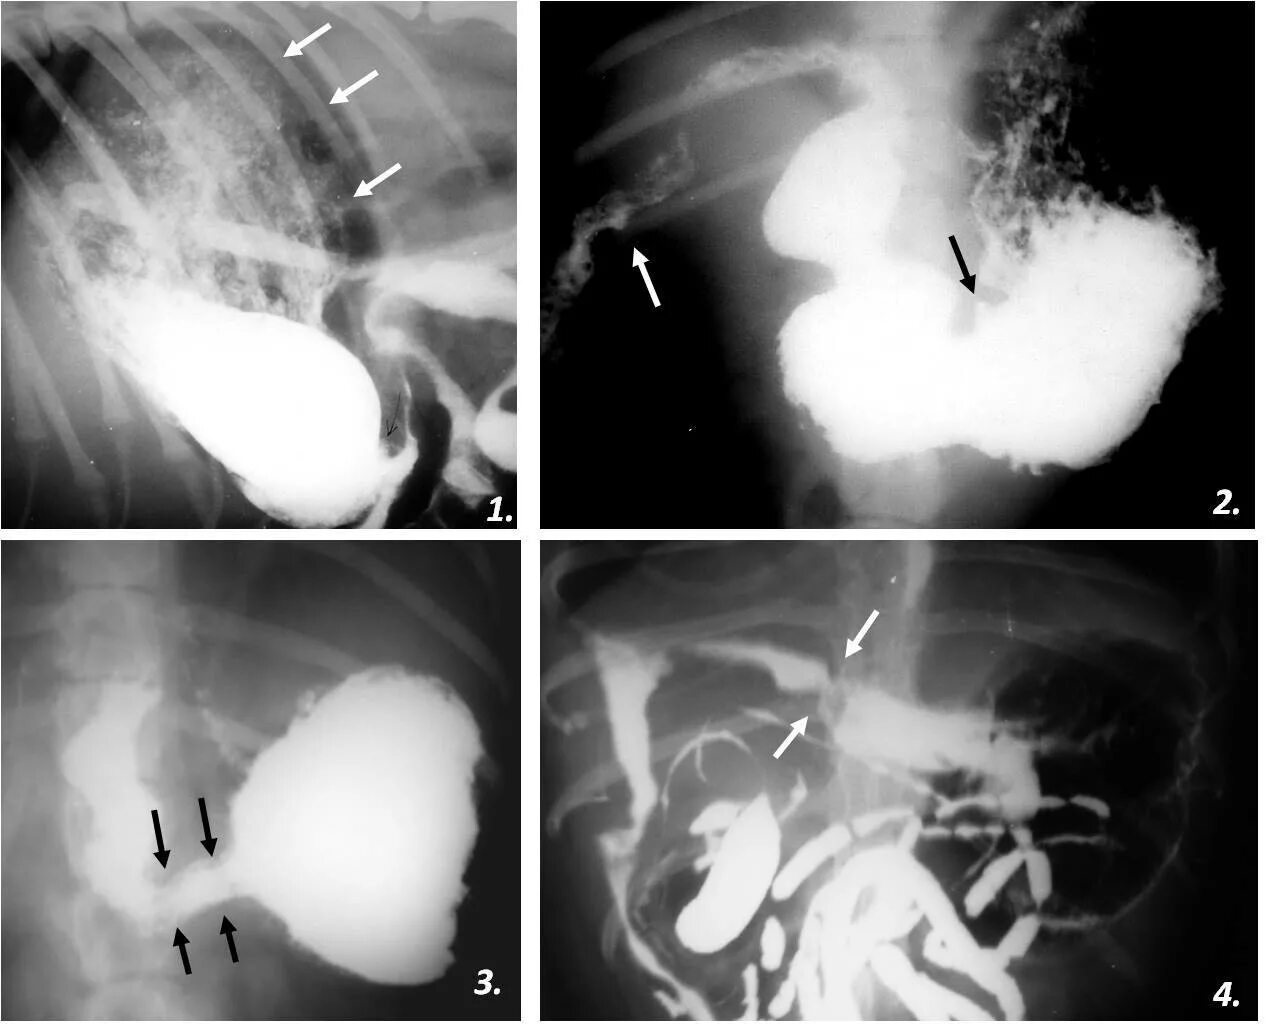

Стеноз спазм